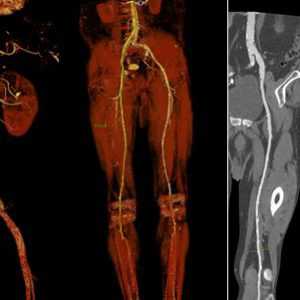

КТ-ангиография сосудов брюшной полости

КТ-ангиография сосудов брюшной полости считается одним из наиболее современных методов определения состояния здоровья сосудистой системы в указанной области. Его главным отличием выступает привлечение специального контрастного вещества.

Обычное ультразвуковое исследование не способно предоставить развернутую картину по структуре и общему состоянию сосудов в брюшной области, что способствовало разработке и внедрению технологии ангиографии. Вместе с контрастом получается визуализировать абсолютно все участки сосудистого русла. На основе полученной визуализации доктор сможет определить не только строение больших и мелких сосудов, но также выявить возможные аномалии в близлежащих органах.

Детализированная картина помогает обнаружить даже малейшие просветы, либо выявить внутренние образования, будь то онкологические опухоли или обычные тромбы. Причем изображение настолько подробно, что опытный рентгенолог способен на его основе распознать только-только зарождающиеся заболевания. Особенно актуален поиск недугов на начальной стадии развития для онкологических заболеваний.

Что дает агиография?

После того как контрастный препарат вводят в локтевую вену, он мгновенно добирается до сердца и дальше распространяется по аорте, ее ветвям, а позднее и до капилляров в брюшине, открывая картину состояния:

- почечных сосудов;

- селезеночных сосудов;

- чревного ствола;

- верхней брыжеечной артерии;

- нижней брыжеечной артерии.

Все они, как и капилляры, отвечают за транспортировку питательных веществ к внутренним органам брюшной полости. Как только указанные кровяные пути выходят из строя, орган перестает выполнять свои обязанности должным образом, что приводит к резкому ухудшению самочувствия. Обнаружить первоисточник всех проблем позволяет тщательная визуализация, на основе которой можно выяснить следующие характеристики:

- анатомические особенности брюшных сосудов вне зависимости от размеров;

- аномалии врожденного или приобретенного типа, вплоть до удвоения и недоразвития;

- патологии на разных стадиях развития, включая локальный атеросклероз и расслоение стенок;

- процентное соотношение ступени сосудистого сужения;

- показатели нарушения кровотока;

- описание кровотока, включая скорость и уровень кровенаполнения.

Все это описывает врач-рентгенолог , который в случае экстренной необходимости может отдать заключение с подробным описанием самому пациенту приблизительно через полчаса после проведения тестирования. А уже сам лечащий врач на основе полученных результатов, жалоб, итогов других обследований, данных анамнеза, таких, например, как наследственной предрасположенности, делает конкретные выводы. Кроме определения окончательного диагноза лечащий врач также назначает последующую терапию, включающую консервативные методы и/или хирургическое вмешательство.